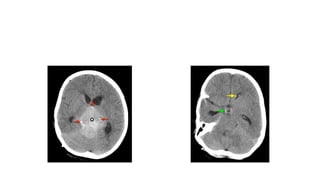

MRI findings

• T1W and T2W:Iso-hyperintense

If cystic necrotic foci (High SI TW2)

• FLAIR: Slightly hyperintense

• DWI/ ADC: Restriction diffusion

• T1W+C: Strong homogenous enhancement

• #18 T1W fat sat + C FLAIR T2W T1W C+ Sag DWI ADC There is a large pineal region mass with moderate enhancement with compression of the tectum resulting in obstructive hydrocephalus. On SWAN imaging the pineal calcification is confirmed to be placed centrally. On T2 the pineal mass is hyperintense. Diffusion-weighted imaging (DWI) shows restriction with low apparent diffusion coefficient (ADC) values.